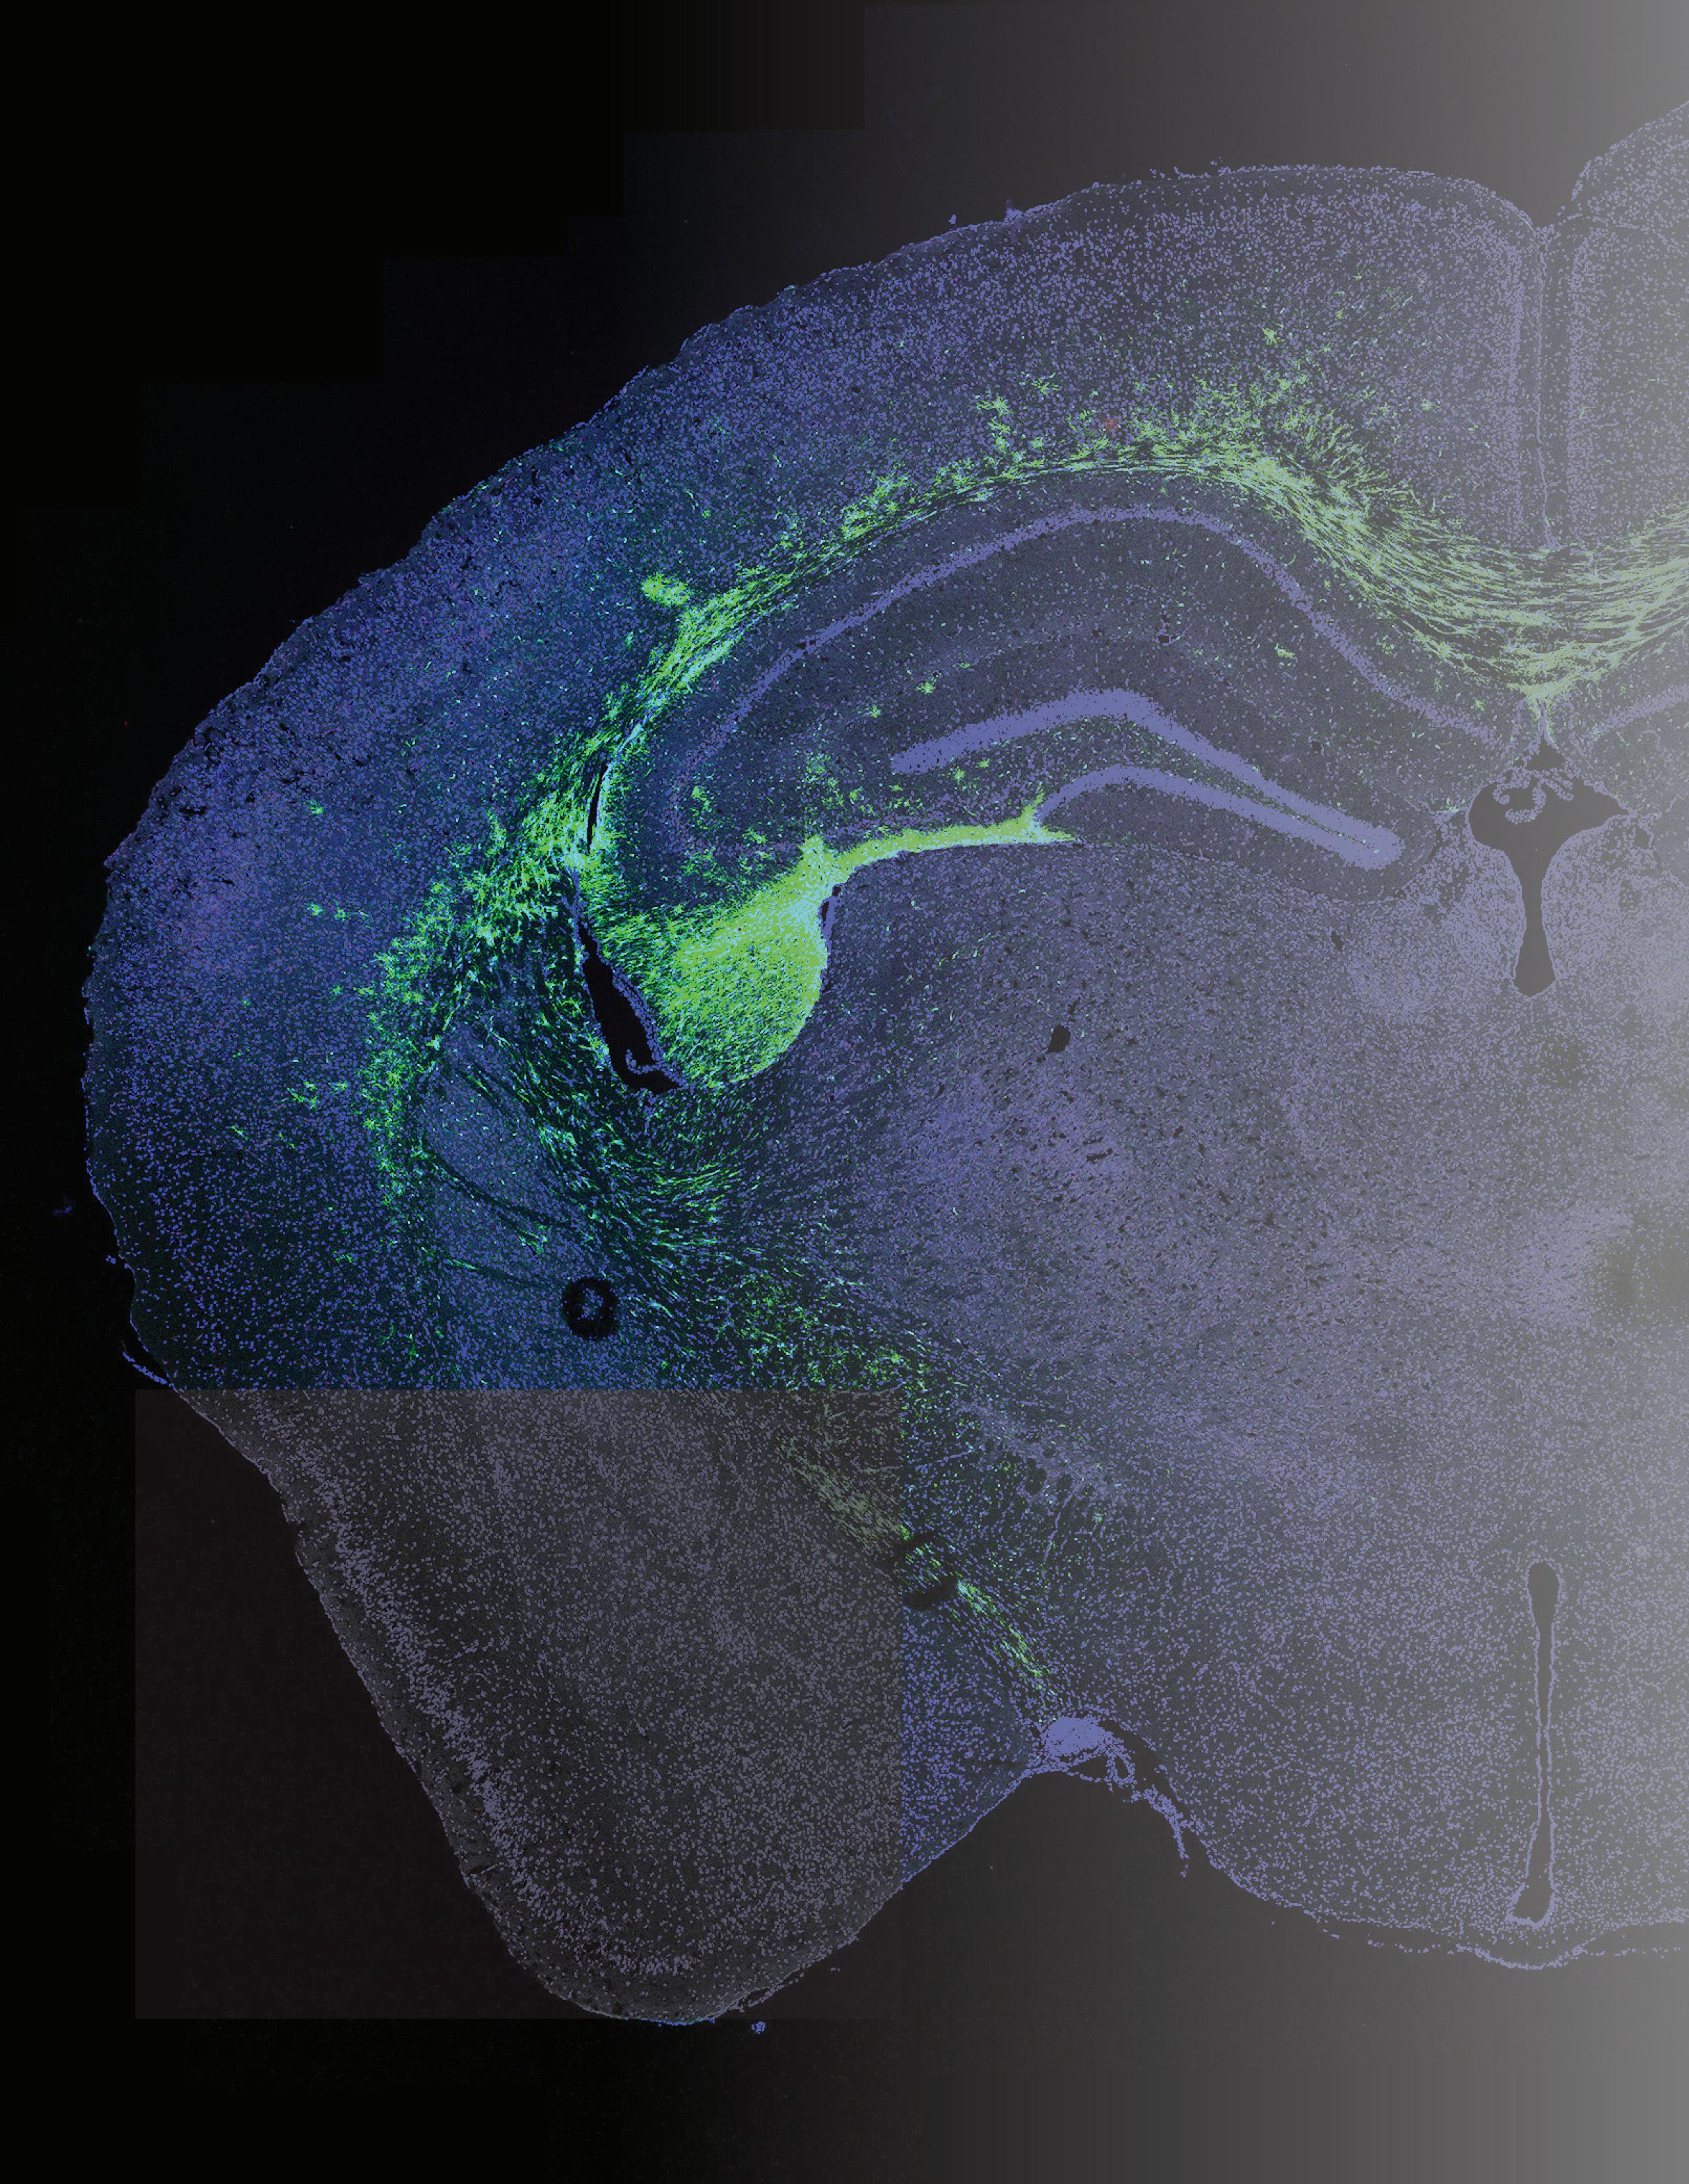

This page: Fluorescent-labeled neural stem cells (green) are transplanted into the memory centers of a mouse brain with Alzheimer’s disease (blue). Dr. Chen is investigating the mechanisms by which stem cells may improve memory and cognition.

Facing page: Dr. Chen’s research uses adult patient-donated cells (e.g., skin cells) that are reprogrammed in the lab to create induced pluripotent stem cells and eventually neurons. This allows for controlled experiments to define disease mechanisms. A future goal is to “repair” these neurons and transplant them back to patients, enabling a patient-specific treatment for neurodegenerative disease.

I am interested in understanding how neural circuits become dysregulated in neurodegenerative diseases like Alzheimer’s disease and amyotrophic lateral sclerosis (ALS). Increasing evidence shows that in these diseases, neuronal activity becomes overactive and hyper-synchronized – like a car with the gas pedal stuck down – leading to abnormal signaling, neuronal exhaustion, and cell death. The cause may be due to issues with inhibitory interneurons, which are local short-range neurons that typically regulate and “brake” neural activity. We are investigating potential causes of interneuron dysfunction and finding ways to reverse these abnormalities through methods based on induced pluripotent stem cells (iPSCs). Essentially, we are investigating a therapy to restore proper interneuron regulation of neural circuits by generating iPSCs from an adult donor’s cells (e.g., skin cells) and transforming them into “corrected” interneurons to be transplanted back into the same patient.

We have published multiple papers demonstrating that stem cell therapy improves cognitive function in animal models of Alzheimer’s disease. Our findings suggest that the stem cells act by normalizing signaling from inflammatory cells in the brain. Additionally, we have optimized the immunosuppression regimen used in these stem cell transplant experiments to improve cell survival while minimizing animal stress and side effects.

Currently, we are establishing an in vitro model of interneurons using iPSCs from Alzheimer’s disease and ALS donors. This model would allow us to study how interneurons degenerate in a controlled experimental manner, avoiding the invasiveness of direct animal or human studies. By identifying key pathways that go awry in diseased interneurons, we can target these pathways for pharmacologic treatment or gene therapy. For example, we have observed significant disruption in genes related to mitochondrial function and energy production within diseased interneurons. Therefore, we may be able to use existing drug compounds to restore mitochondrial energy function and normalize proper neural circuit regulation in neurodegenerative diseases.